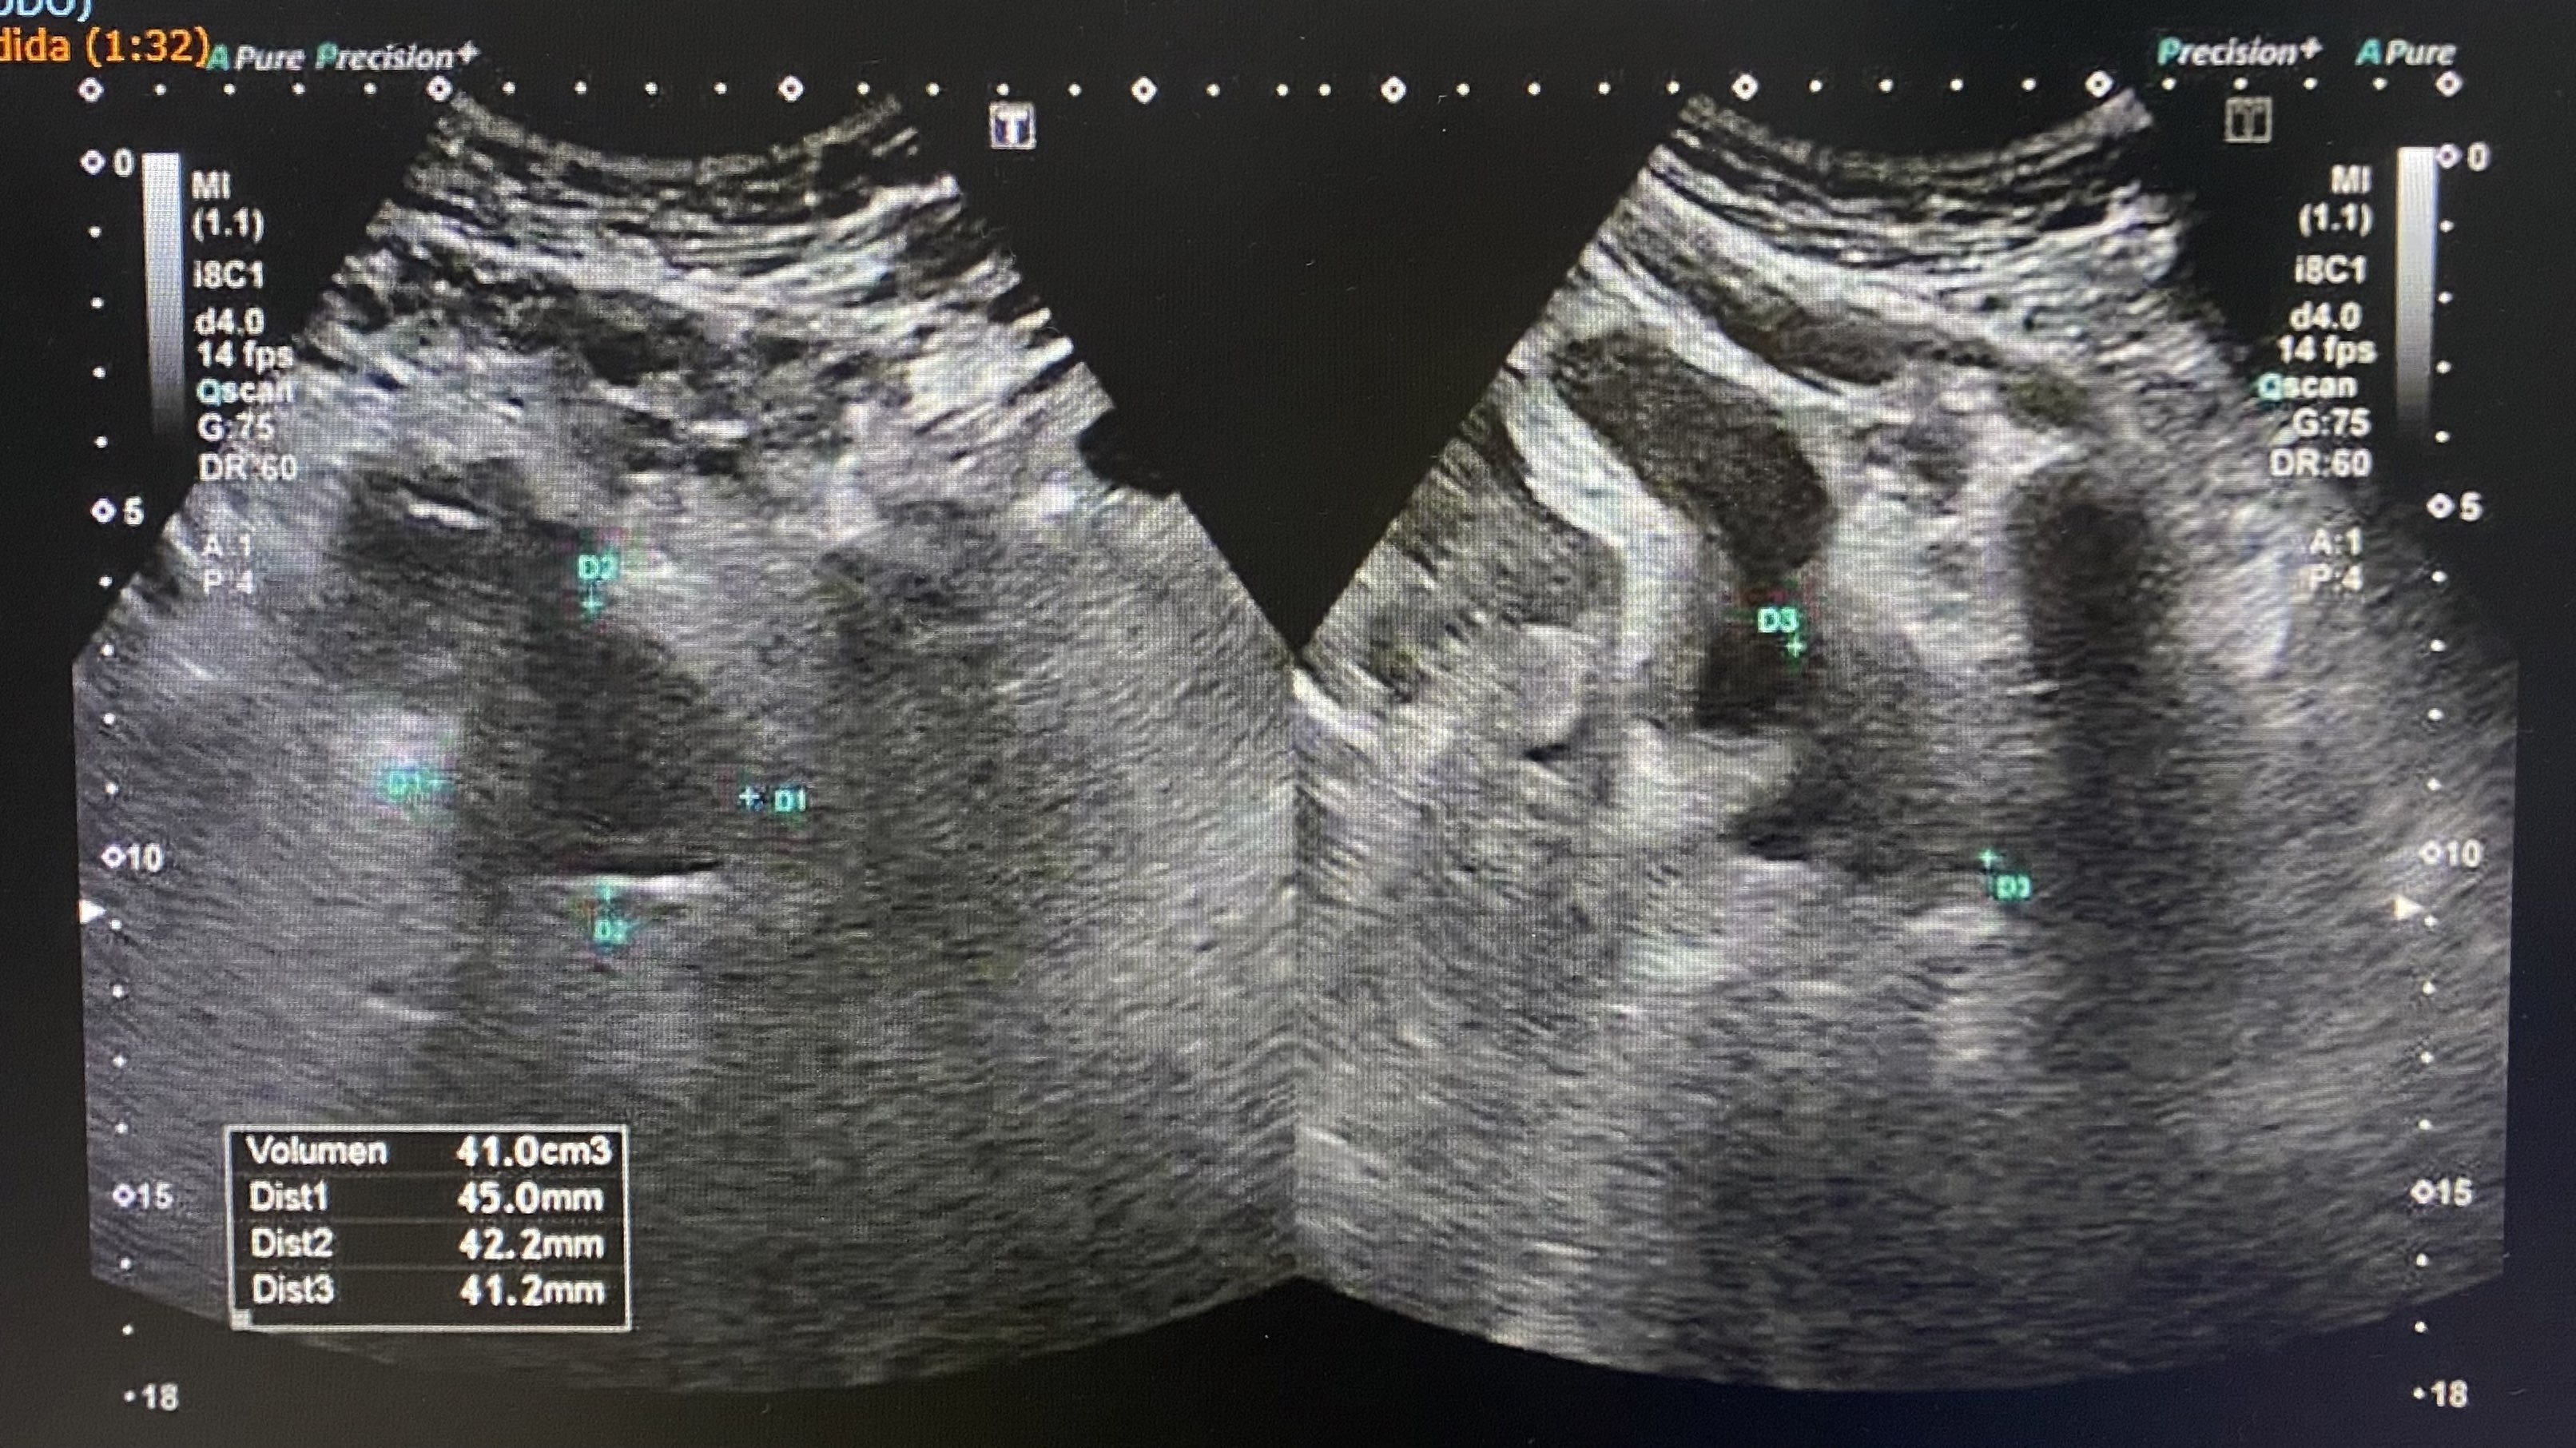

En ecografía de control dos meses después se observa una ligera dilatación pielocalicial del riñón izquierdo y normalidad del derecho (imagen 3), además se consigue objetivar la próstata aumentada de tamaño (imagen 4).